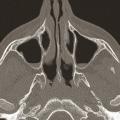

Rhinosinusites chroniques de l’adulte : nouvelle définition, nouveau diagnostic

La rhinosinusite chronique occupe une place centrale en pathologie rhinologique de l’adulte. Ce terme de « rhinosinusite chronique » a longtemps fait l’unanimité chez les rhinologistes qui se fondaient : sur l’unicité apparente de la muqueuse respiratoire du nez ; sur une communauté d’origine de l’ethmoïde et des…